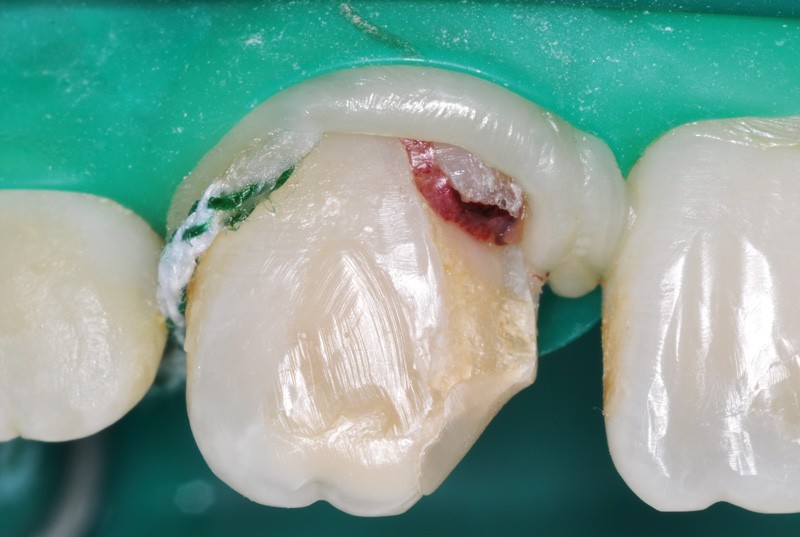

a à d Jeune patiente âgée de 8 ans, adressée suite à un traumatisme survenu 3 semaines auparavant, pour l’extraction de sa 21. La vue clinique montre un saignement ligamentaire, une mobilité coronaire et une fracture coronaire amélodentinaire longitudinale partant de l’angle mésial et se poursuivant en direction radiculaire sous-gingivale (a). Un test de vitalité positif indique que la dent est vitale, la radiographie permet de poser le diagnostic de fracture coronoradiculaire, et d’objectiver l’immaturité radiculaire (stade 8 de Nolla) (b). Une contention est mise en place et la plaie dentinaire coronaire est scellée au mieux par collage afin de limiter le risque d’une complication infectieuse (c). A 15 jours la dent est vivante et aucune complication n’est apparue (d). La patiente est revue après 3 mois pour déposer la contention, le test de vitalité est positif, et la radiographie de contrôle montre une apexogenèse en cours (e). Cependant la gencive s’est invaginée dans le trait de fracture (f). La zone est débridée sous microscope (g) puis scellée et reconstituée à l’aide d’un adhésif SAM et d’un composite fluide (h). Le contrôle radiographique à 6 mois est satisfaisant (i). Ce cas clinique illustre le fort potentiel des pulpes jeunes et du ligament alvéolodentaire à résister aux agressions et à assurer les fonctions dentinogénétiques et l’édification radiculaire.